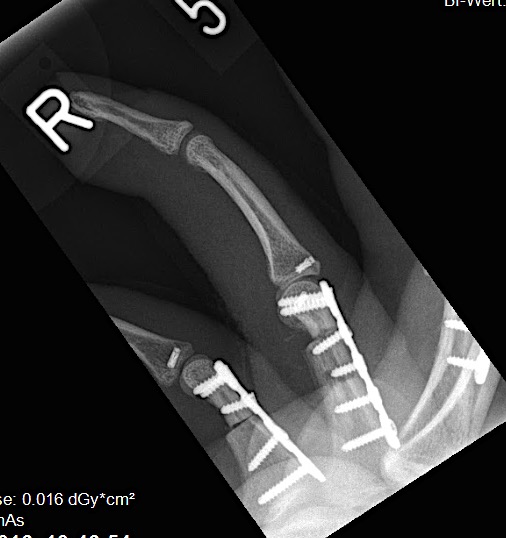

Case 2:

A 20-year-old male suffered a complex multi-digit injury of the right hand requiring revascularization and stabilization of both proximal phalanx and PIP joint fractures (Figs 5 - 8). Multiple plates, including the rotation correction plate from the 1.5 module of the VA Locking Hand System were used for fixation. The Variable Angle Locking system is ideal when only two screws, either proximal or distal, are able to be inserted due to space limitation.

One major advantage of variable angle technology in very distal phalangeal fractures is the ability to be extremely flexible with a wide range of fixation options. Freedom of implant placement assists early mobilization, vital in these complex fractures with associated soft-tissue trauma.